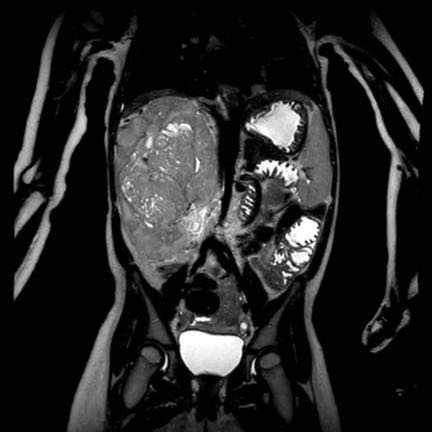

Ca lâm sàng 1

Hình ảnh chuỗi xung T2W mặt phẳng coronal cho thấy một khối u không đồng nhất ở thận trái với các thành phần nang nhỏ.

Khối u ngấm thuốc kém hơn so với phần nhu mô thận bình thường còn lại ở ngoại vi.

Các thành phần đặc của khối u cho thấy hạn chế khuếch tán rõ rệt (mũi tên).

Đây là u Wilms ở bé trai năm tuổi. Hóa trị tiền phẫu được thực hiện theo phác đồ Umbrella của SIOP-RTSG, sau đó tiến hành cắt thận.